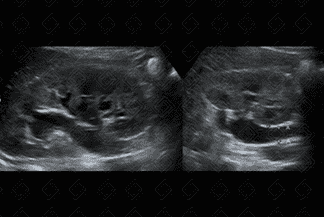

Texto alternativo para a imagem Figuras 4 e 5. Créditos: Elazir Mota - Rio de Janeiro/RJ

Descrição das figuras 4 e 5: Ultrassonografia das vias urinárias. No terço distal do ureter direito, no óstio ureterovesical, observa-se imagem ecogênica, com sombra acústica posterior (seta branca), compatível com cálculo, medindo 0,5 cm.

• Ultrassonografia das vias urinárias: Muito útil em mãos treinadas, ou seja, um médico radiologista experiente, onde observa-se imagem ecogênica com forte sombra acústica posterior no interior do ureter. Muito utilizado na população pediátrica e nas gestantes;